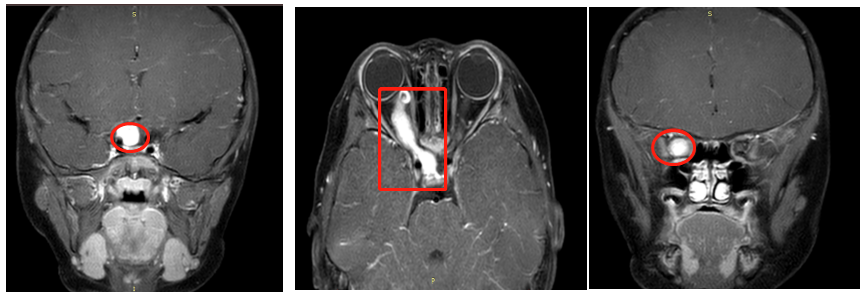

中脑胶质瘤被认为“可能是人体内较少导致病人死亡的肿瘤”,患者死亡多是由于肿瘤引起的阻塞性脑积水,而不是肿瘤本身。磁共振成像(MRI)是诊断中...